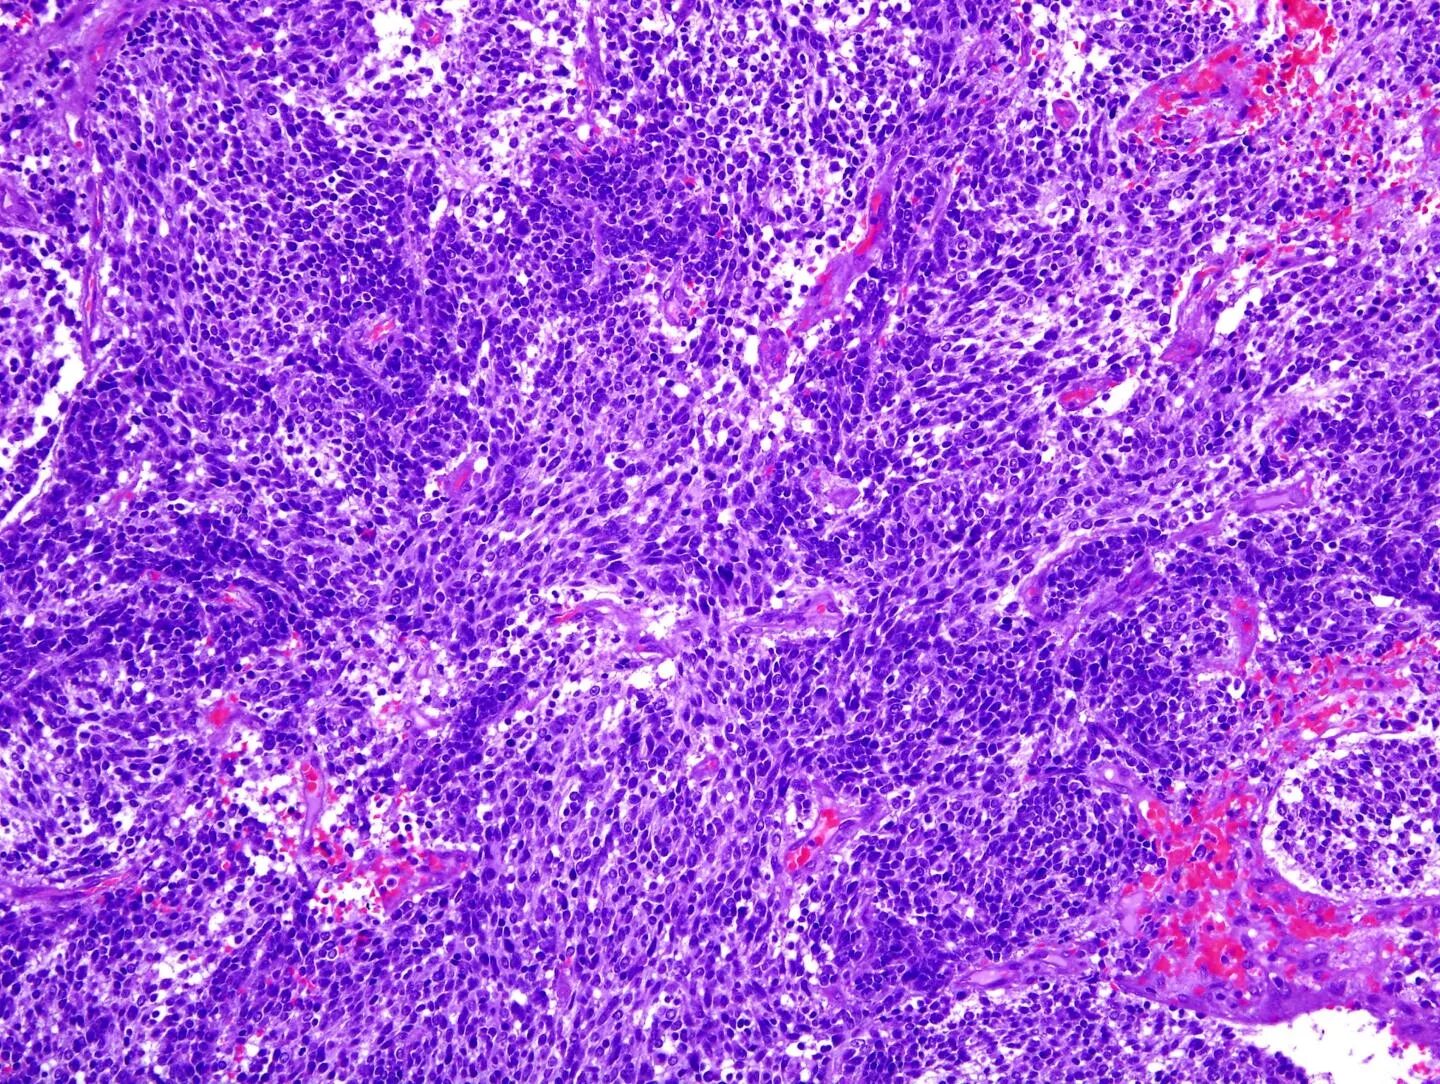

Гистологические варианты